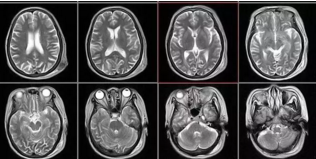

2、頸椎腰椎——最佳選核磁,次選CT

6.png

頸椎病、腰椎間盤突出等椎間盤疾病需要觀察椎間盤與相應(yīng)的神經(jīng)根,要想更好觀察這些軟組織,最優(yōu)選擇就是核磁。同樣,對于關(guān)節(jié)、肌肉、脂肪組織檢查,核磁也是首選。